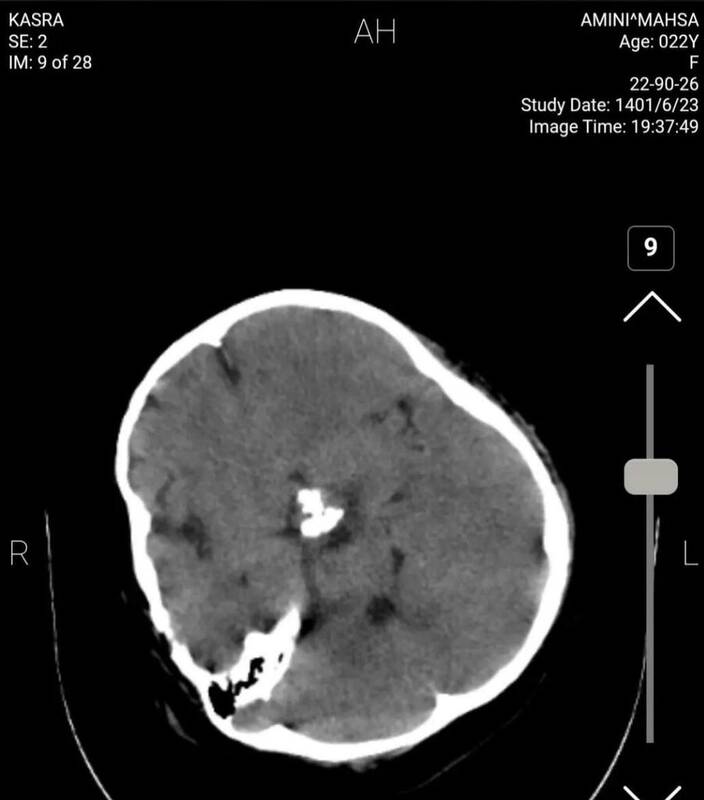

برای بررسی علمی این موضوع با تعدادی از پزشکان مغز و اعصاب و رادیولوژیست گفتوگو کردیم تا به صورت علمی این موضوع را بررسی کنیم. این متخصصان معتقدند بررسیهای سی تی اسکن بیمارستان نشان میدهد هیچ شواهدی از ضربه به سر و خونریزی در این تصاویر به چشم نمیخورد.

یک متخصص جراحی مغز و اعصاب گفت: بررسیها نشان میدهد که بیمار در گذشته جراحی در ناحیه سر انجام داده است اما براساس شواهد موجود از روی سیتیاسکن نمیتوان فهمید که جراحی دقیقاً مربوط به چند سال قبل است.

همچنین شواهد کرانیتومی فرونتوتمپورال قبلی همراه با آتروفی مختصر عضلانی و تغییرات بافت نرم در محل جراحی بیمار مشهود است.

یکی دیگر از پزشکان مغز و اعصاب نیز جراحی تومور بیمار را تایید میکند. به گفته این متخصص مغز و اعصاب متاسفانه برخی از افراد با دیدن تصاویر ناقص سی تی اسکن درفضای مجازی اقدام به اعلام نظر کردهاند اما واقعیت این است که در تصاویر کامل اثری از شکستگی نیست و این رسانه سعودی تصاویر را از زاویهای منتشر کرده است که شکستگی به نظر برسد.

برای بررسی دقیقتر موضوع سراغ پزشکی دیگری رفتیم. متخصص مغز و اعصاب دیگر میگوید: بیمار در گذشته جراحی سر انجام داده و بخشی از تومور در ناحیه سوپراسلار باقی مانده است. بررسی بیشتر سی تی اسکن بیانگر این است که با توجه به نوع جراحی انجام شده در این ناحیه وقوع دیابت بیمزه در بیمار دور از انتظار نیست و با توجه به آتروفی لوب فرونتال راست احتمال صرع را نمیتوان برای بیمار رد کرد هرچند اساساً تشخیص صرع یا دیابت بیمزه با سیتیاسکن مقدور نیست.